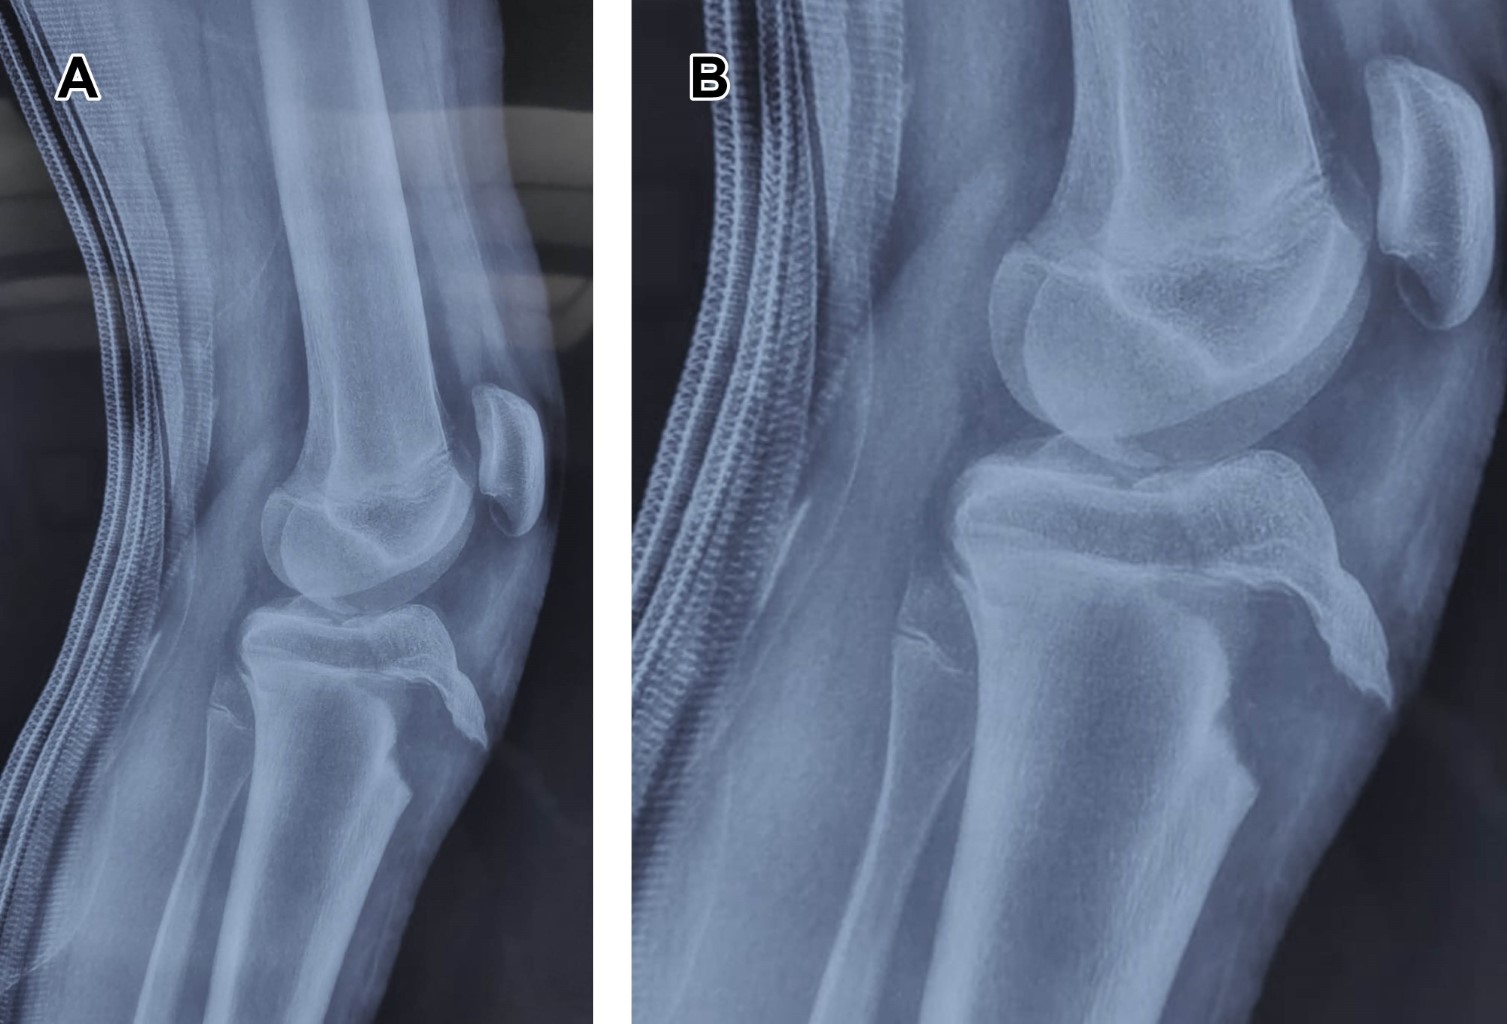

Masculino de 12 años, con estatura de 178 cm, jugador de baloncesto desde los ocho años; quien, realizando ejercicios de marcha en cuclillas, en el momento de cambiar a posición de pie, refiere dolor intenso en rodilla izquierda, acompañado de chasquido, deformidad, e imposibilidad para la función. Es trasladado a urgencias, efectuando diagnóstico de fractura avulsión de tuberosidad anterior de la tibia, corroborando ATT tipo III de Watson y Jones (Figuras 1 y 2), se realizó reducción y osteosíntesis (Figura 3).

El tratamiento es: reducción anatómica del fragmento, la restitución de la superficie articular tibial y la restauración del mecanismo extensor; la reducción cerrada e inmovilización en avulsiones completas sin desprendimiento de la epífisis con desplazamiento mínimo (< 2 mm), y reducción abierta y fijación interna en el resto de los casos. La fractura que se extiende hacia la superficie articular de la rodilla debe ser tratada mediante reducción abierta con restauración anatómica de la superficie tibial articular.3

Figura 3